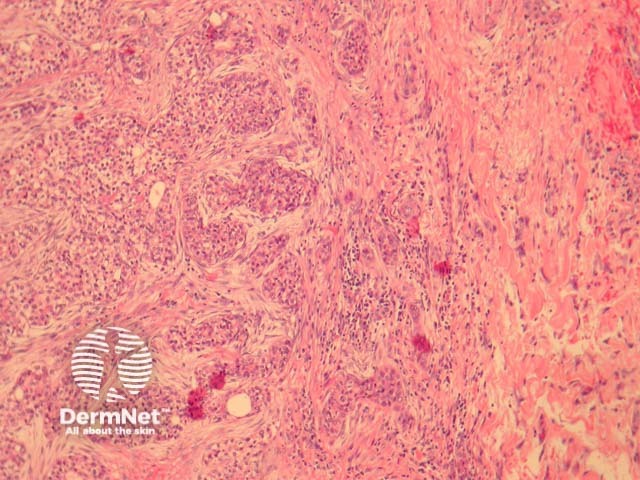

Hidradenocarcinoma may arise within a pre-existing hidradenoma. Hidradenocarcinomas are often large nodular dermally based tumours which may invade the subcutaneous fat (figure 1) and irregularly infiltrate the surrounding dermis (figure 2). The tumour cells are epithelioid and may often show clear cell changes (figure 3), or may appear basaloid, or have an eosinophilic cytoplasm (figure 1). There may be foci of squamous differentiation and duct formation (figure 2). There may be necrosis (figure 4).

Figure 1